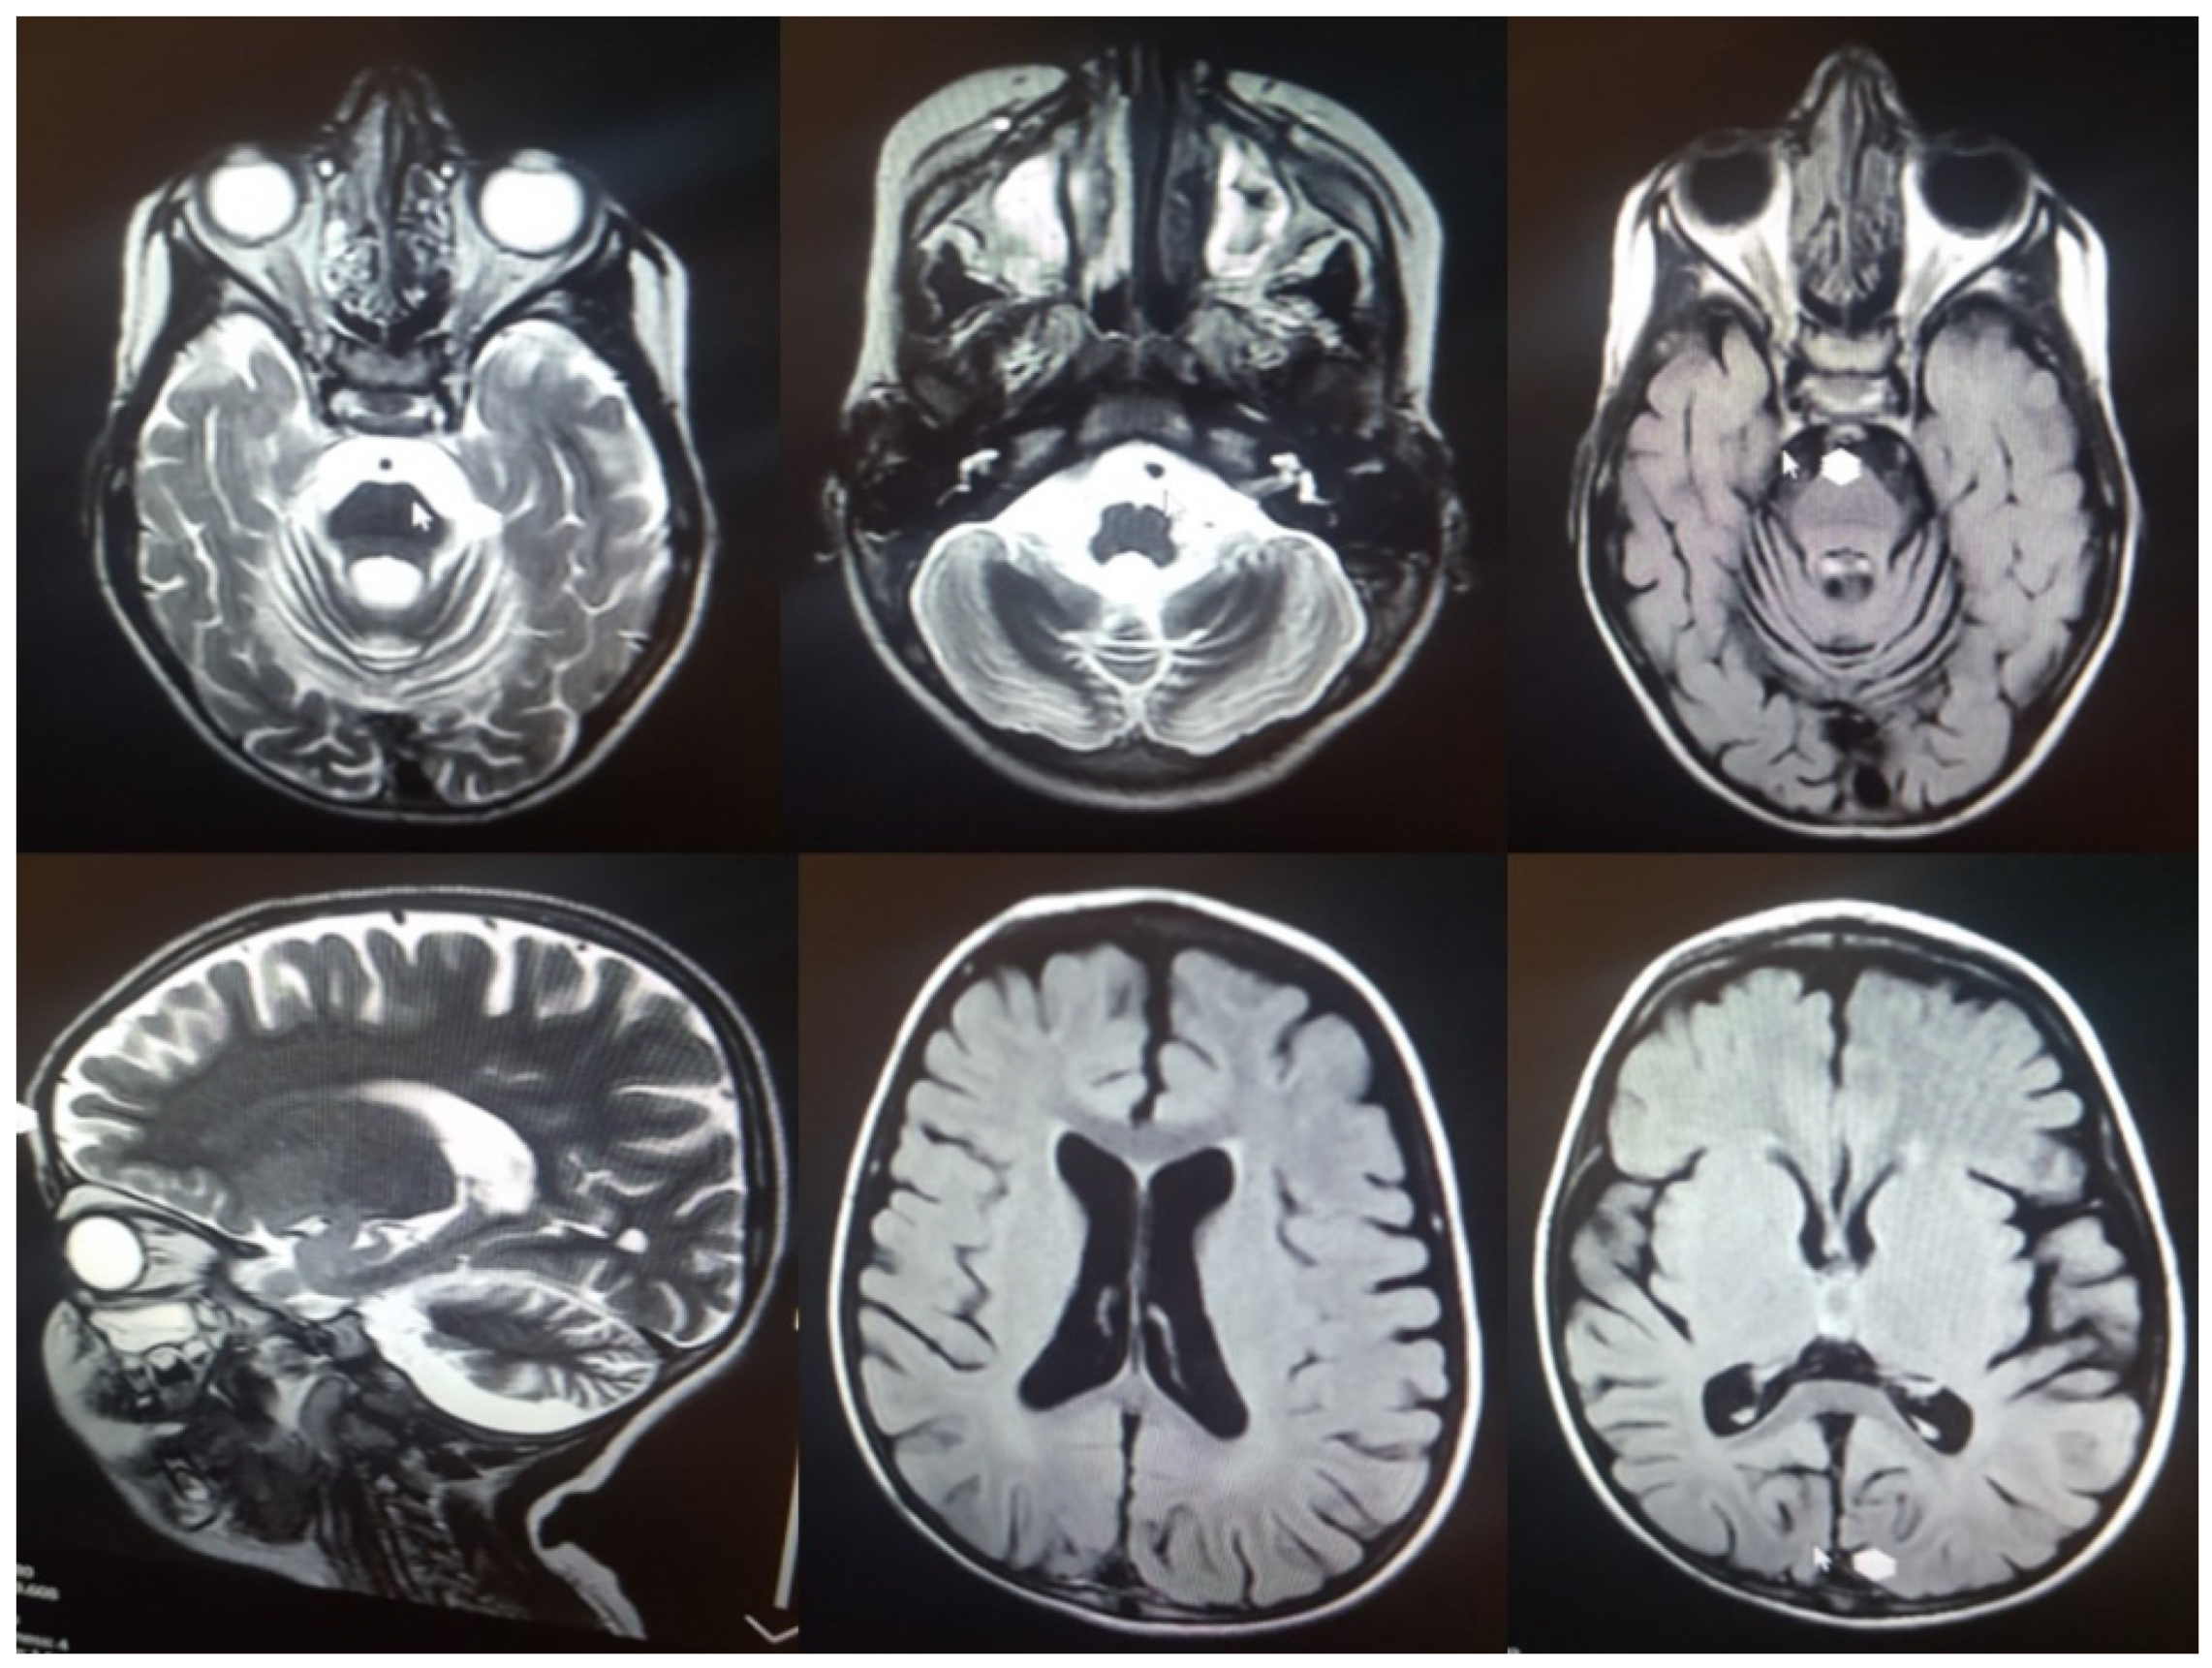

| 5y/M | Seizures/4y | Cerebellar atrophy, ataxia, epilepsy, vision loss, spasticity, tremor, motor difficulties, swallowing problems, sleep disorder, cognitive decline, language regression | yes | c.C832T | p.Q278X | 7 | PVS1, PM2 | LP | Hom | Iran | This study |